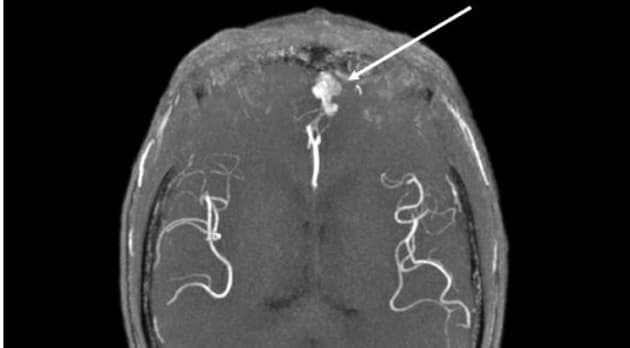

Bør man screene patienter med mb. Osler for cerebrale arteriovenøse malformationer?

Screening for cerebrale arteriovenøsemalformationer ved mb. Osler